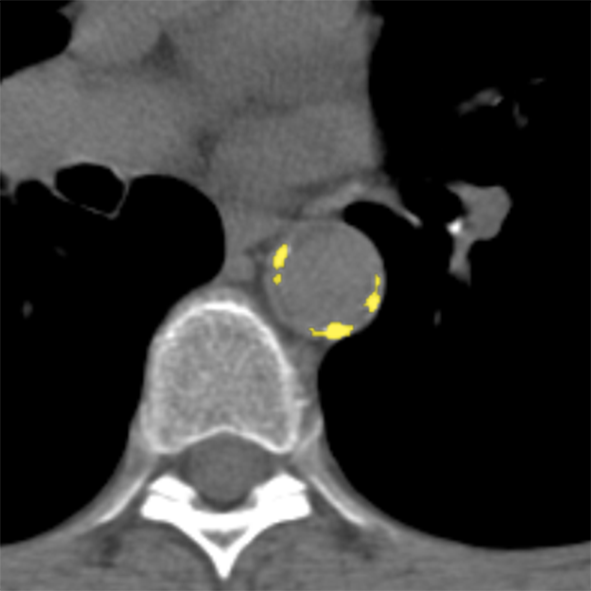

To establish a reference standard, calcifications were manually labeled in all scans. Scans were distributed among four trained observers and one radiologist with extensive experience in calcium scoring. To measure interobserver agreement, a subset of 100 scans (four scans from each of the 25 different scanner models and reconstruction algorithms) was annotated by two of the trained observers and the radiologist. Manual calcium annotation usually requires the observer to select only a single voxel per lesion. The lesion is then automatically segmented with region growing using the standard intensity threshold of . In low-dose scans, however, intensity based region growing often leads to large amounts of noise being segmented with the calcium (Figure 1). Moreover, it can lead to the spine and ribs being segmented together with calcium, or calcifications in arteries branching off the aorta being segmented together with calcium in the aorta. The observers therefore marked calcifications voxel-by-voxel () in the coronary arteries, the aorta and the aortic and mitral valves, including the annulus. Coronary calcifications were labeled as either left anterior descending artery (LAD), left circumflex artery (LCX) or right coronary artery (RCA). The left main coronary artery was considered part of LAD because these are difficult to distinguish on ungated scans. Motion artifacts caused by calcifications were annotated as calcifications because an exact separation of true calcification and artifact is often not possible. Depending on the amount of calcification and the image quality, the annotation effort varied from 5–10 minutes for images with soft reconstruction and little calcium to 60–90 minutes for images with sharp reconstruction and/or large amounts of calcium.

The performance of automatic CAC detection was evaluated based on scores per artery and per subject. Per artery and per subject sensitivities, average false positive volumes and F1 scores for CAC detection are listed in Table II. Examples of detected calcifications are shown in Figure 6.

(a)

(b)

(c)

(d)

(e)

(f)

(g)

(h)

(i)

(j)

(k)

(l)

For CAC and TAC detection, the method achieved a performance close to the level of interobserver agreement. The method was furthermore able to separate calcifications in the coronary arteries into LAD, LCX and RCA calcifications (Figure 6 (f)). The method as well as the observers were more successful in identification of LAD and RCA calcifications than LCX calcifications. The course of LCX is particularly difficult to follow in non-contrast scans. Hence, LCX calcifications can be difficult to differentiate from LM and LAD calcifications (Figure 6 (l)), as well as from those in the mitral valves. In comparison to CAC and TAC, calcifications of the aortic and mitral valves were less common in our dataset. Performance of the automatic method was below the performance of CAC and TAC detection. However, this is also a difficult task for experts. The observers especially disagreed on mitral valve calcifications, which is in line with findings of previous studies [45]. The disagreement is mainly caused by confusion with LCX calcifications and the lack of soft tissue contrast in the mitral valve region. For the aortic valve, confusion with TAC was the most common cause of disagreement.

False positive detections were mostly caused by mislabeling of calcifications with respect to their location (e.g., LAD and LCX), low-dose and motion artifacts, and other calcifications such as calcified lymph nodes or calcifications in other vessels (Figure 6 (i)–(k)). False positive detections outside the heart and the aorta occurred infrequently and usually in proximity to the heart or the aorta. This demonstrates that CNN1 was able to implicitly learn to recognize the typical spatial context of calcifications in the image. The individual evaluation of CNN1 additionally showed that CNN2 substantially contributes to reducing false-positive detections while maintaining a high sensitivity. However, future work could aim at unifying the two networks into a single network.

False negative detections were sometimes partially misclassified lesions (Figure 6 (h)–(i)). Partial misclassification can occur because the method performs voxel classification rather than the standardly used lesion classification. Even though voxel labeling occasionally causes partial misclassification of calcifications, it enables splitting of calcifications that are contained in more than one arterial bed, such as those partly located in the aorta and partly in the coronary arteries (Figure 6 (f)). Assigning a calcification that is partially contained in the aorta to the coronary artery could affect cardiovascular risk categorization. Similarly, assigning LM calcifications to the aorta would result in missing high risk lesions. To the best of our knowledge, this is the first method enabling splitting of the calcifications according to their arterial bed.